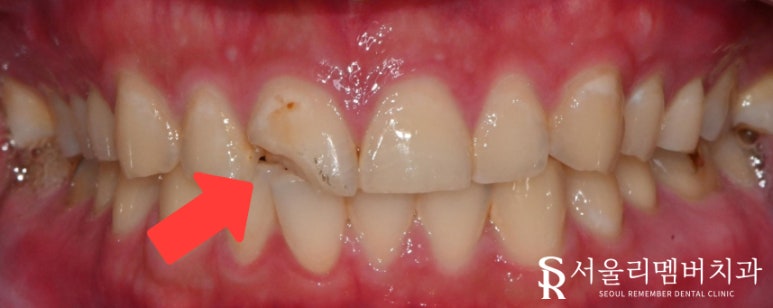

넘어지는 동시에 앞니에 충격이 가해져

이가 부러졌다며 내원하셨습니다.

사당동 치과 에서 살펴본 결과,

파절 부위가 적지 않았으며

라미네이트는 적합하지 않다는 판단이 들었는데요.

전체를 씌우는 크라운이 필요해 보입니다.